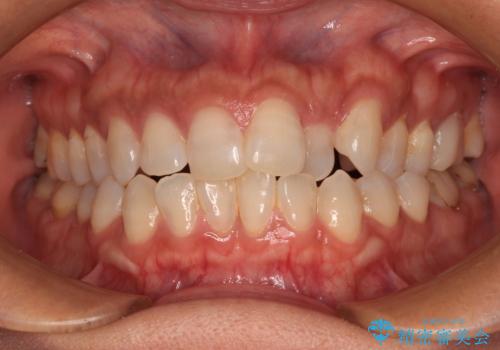

捻れて前に出ている前歯 ワイヤー装置での非抜歯矯正